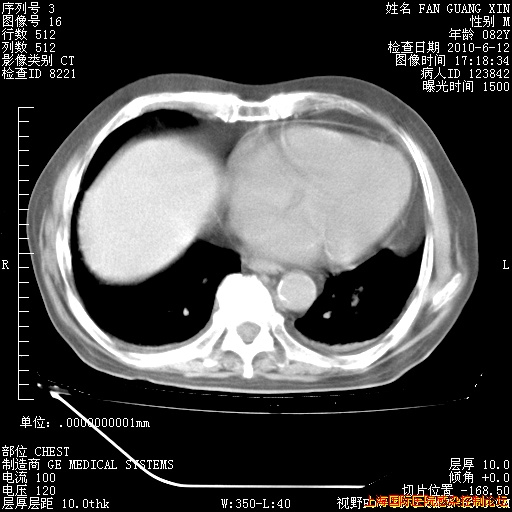

补发6月12日肺部CT肺窗

6月12日肺窗

6月12日纵膈窗